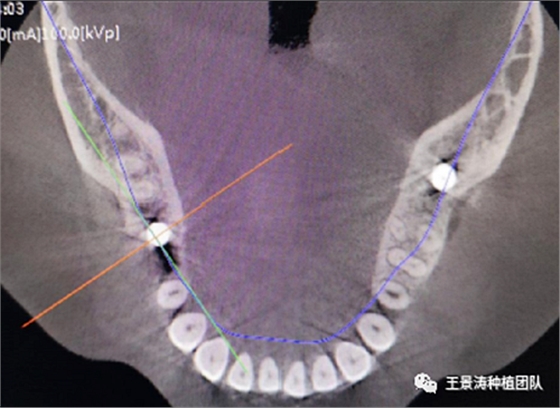

其次初期穩(wěn)定性的獲得,前牙美學(xué)區(qū)種植體的初期穩(wěn)定性主要是依靠腭舌側(cè)骨板及基底骨來獲得的。后牙區(qū)的穩(wěn)定性主要依靠多根牙的牙槽間隔及根尖到重要解剖位置的高度的骨質(zhì)獲得(主要是竇嵴距和管嵴矩的高度,還要參考植入種植體的長度),因此術(shù)前仔細(xì)測量牙槽間隔與根尖至重要解剖結(jié)構(gòu)的高度是后牙即刻種植的關(guān)鍵因素之一。

左側(cè)下頜第二磨牙及右側(cè)下頜第一磨牙同時(shí)即刻種植病例?;颊吣贻p女性,無系統(tǒng)性疾病。37及46殘冠及殘根,且46劈裂,無法冠修復(fù),必須拔除。37根尖慢性炎癥,大量肉芽組織存在,46根分叉較高,根分叉骨質(zhì)尚可。CBCT示:根尖骨質(zhì)至下牙槽神經(jīng)管距離可滿足種植體的初期穩(wěn)定性,遂考慮即刻種植,并在種植體周邊填入骨粉并覆蓋骨膜,雙側(cè)的種植體初期穩(wěn)定性相差無幾,但考慮到37根尖慢性炎癥較大,遂給予埋入式種植。